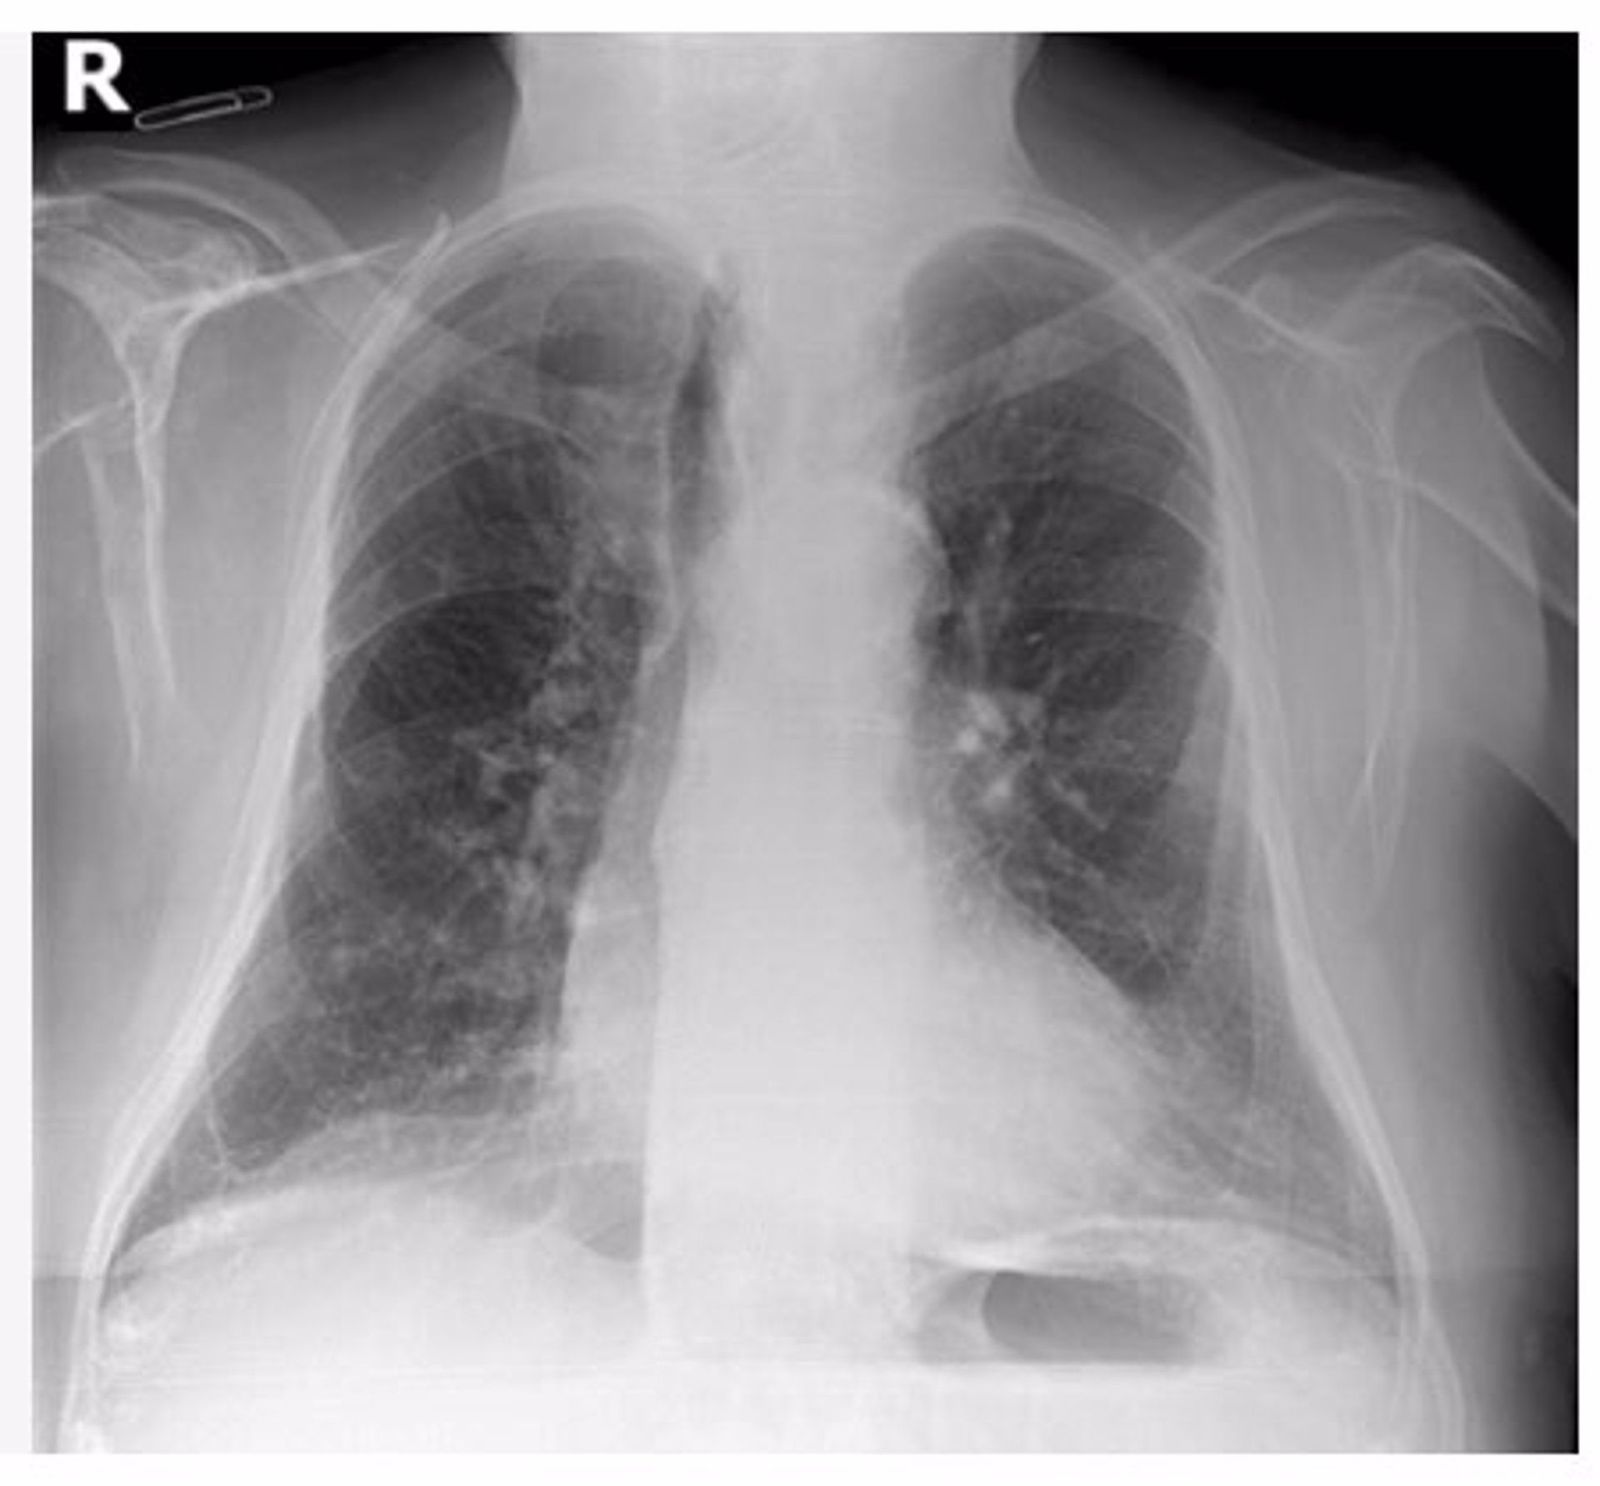

Radiografía de tórax | Europa Press

Personal científico de la Fundación para el Fomento de la Investigación Sanitaria y Biomédica de la Comunitat Valenciana (Fisabio), en colaboración con la Society for Imaging Informatics in Medicine (SIIM), ha convocado un 'challenge' o desafío científico a nivel internacional para la detección de COVID-19 en radiografías de tórax a través de Inteligencia Artificial (IA).